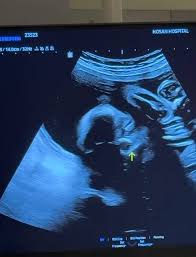

| 2025년 8월 25일 | **쌍둥이 초음파 영상 공개**. 아들 머리 크기가 딸보다 3주 앞선다고 언급하며 유쾌한 심경 토로. | 개인 SNS |

**지소연** 씨는 과거 **난임**과 유산이라는 아픔을 겪었음을 솔직하게 고백하며 많은 이들의 공감을 얻었습니다. 그런 그녀가 2023년 첫딸을 얻은 데 이어, 이번에는 **남매 쌍둥이 임신**이라는 두 배의 기쁨을 맞이하게 된 것이죠. 이번 **초음파 공개**에서 아들의 머리 크기가 딸보다 3주 앞서고 있다는 사실을 유쾌하게 전하며 딸의 성장을 걱정하는 모습은, 아이들을 향한 엄마의 깊은 사랑과 더불어 그녀가 겪어온 쉽지 않은 과정을 짐작게 합니다. 이는 수많은 **난임** 부부들에게 희망과 위로를 전하는 메시지가 되고 있습니다.

A. **지소연** 씨는 현재 **남매 쌍둥이**를 임신 중입니다. 2023년 첫딸 출산 이후 둘째 임신 소식이며, 건강하게 출산을 준비하고 있습니다. **초음파 공개**를 통해 아들 머리가 딸보다 3주 크다는 유쾌한 소식도 전했죠.